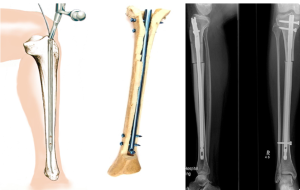

Стержневой аппарат относится к односторонним многоплоскостным аппаратам внешней фиксации и состоит из двух опорных пластин с продольными прорезями, в которых установлены распорные рамки со стяжными болтами и держателями стержней. Пластины и распорные рамки аппарата изготовлены из высокопрочного рентгенопрозрачного углепластика, применяемого в оборонной и аэрокосмической промышленности, который позволяет контролировать точность закрытой репозиции во всех проекциях как в процессе оперативного вмешательства, так и в послеоперационном периоде. Кроме того, наличие углепластиковых элементов значительно снижает вес конструкции. Аппарат позволяет вводить стержни, руководствуясь исключительно характером перелома и не ограничивая хирурга в выборе плоскости и угла введения стержня, причем не только в пределах ширины корпуса аппарата, но и вне его благодаря наличию специальных выносных кронштейнов. Держатели стержней в аппарате свободно перемещаются и самоустанавливаются в процессе репозиции, не препятствуя устранению всех видов смещений костных отломков, поэтому они были названы «плавающими» [2]. Аппарат обеспечивает взаимное репонирование костных отломков по 6 степеням свободы, а после репозиции затяжкой двух гаек на каждом держателе стержня фиксируются все 6 степеней свободы, что обеспечивает прочную и стабильную фиксацию костных отломков до полной консолидации перелома.

Спице-стержневой аппарат состоит из основы в виде стержневого аппарата, а также двух соединенных друг с другом выносных кронштейнов, фиксирующихся к корпусу аппарата на одном из его концов и образующих полукольцо. На конце корпуса и свободном конце полукольца установлены фиксаторы, расположенные в одной плоскости и выполненные в виде спицедержателей со спиценатягивателями, позволяющими регулировать степень их натяжения и создавать встречно-боковую компрессию костных отломков.

Нами применен принципиально новый подход к лечению переломов коленного сустава с использованием стержневого аппарата внешней фиксации. При чрескостном остеосинтезе переломов дистального отдела бедренной кости применялись канюлированные спонгиозные стержни со специальной резьбой для введения в мыщелки через небольшие разрезы, которые сводят к минимуму риск оперативного вмешательства и кровопотери. Стержень выполнен полым для размещения в нем спицы, имеет канавки для выдавливания костной стружки, самонарезающуюся резьбовую часть и упорный буртик для компрессии костных отломков по линии перелома. Применение данного стержневого аппарата малотравматично, операция занимает меньше времени, чем при использовании погружного остеосинтеза и спицевых аппаратов, при этом исключается риск повреждения сосудистонервных стволов благодаря его одностороннему расположению, а создаваемая стабильная фиксация позволяет начинать активизацию пациентов в раннем послеоперационном периоде. Наш опыт показал простоту и безопасность остеосинтеза данным аппаратом, минимальную травматичность операции и высокую стабильность фиксации костных отломков даже у пациентов с остеопорозом.